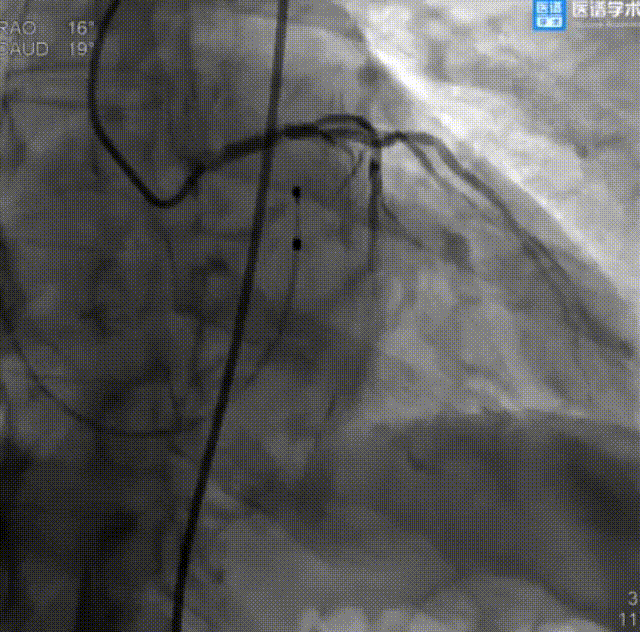

经股动脉主动脉瓣置换术:

主动脉瓣造影,提示有明显反流

导丝成功跨瓣

VitaFlow生物瓣膜成功释放

VitaFlow生物瓣膜植入后即刻造影

球囊后扩

球囊后扩后造影

成功回撤二尖瓣球囊系统和导引鞘后,继续行经股动脉主动脉瓣置换术。术中顺利送入导丝建立入路,导丝成功跨瓣后送入22 mm球囊至主动脉瓣预扩张,后送入TAV27 mm瓣膜至主动脉瓣处。在180 bpm快速起搏的同时释放瓣膜,即刻造影显示中度瓣周漏,遂又送入25 mm球囊至主动脉生物瓣膜处行后扩张,瓣周漏较先前明显减少。术后超声显示平均主动脉跨瓣压差为3 mmHg。